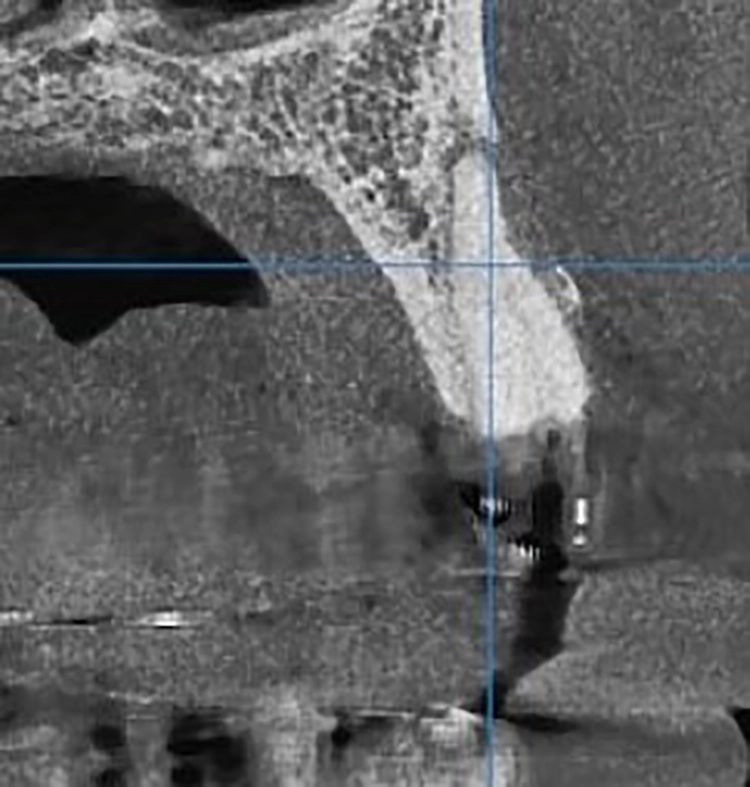

Bei diesem 49-jährigen, allgemeinanamnestisch unauffälligen Patienten liegen diverse ästhetisch störende Zahnstellungsanomalien vor, wobei Zahn 21 bei extremer Elongation frakturierte (Abb. 2a). Nach einer Übergangsversorgung mittels provisorischer Stiftkrone (Abb. 2b) entschied sich der Patient für eine Zahnentfernung bei gleichzeitiger Implantation. Im Ausgangs-DVT (Abb. 2c und d) zeigt sich im Cross-Sectional, wie weit der Processus alveolaris zurückliegt.